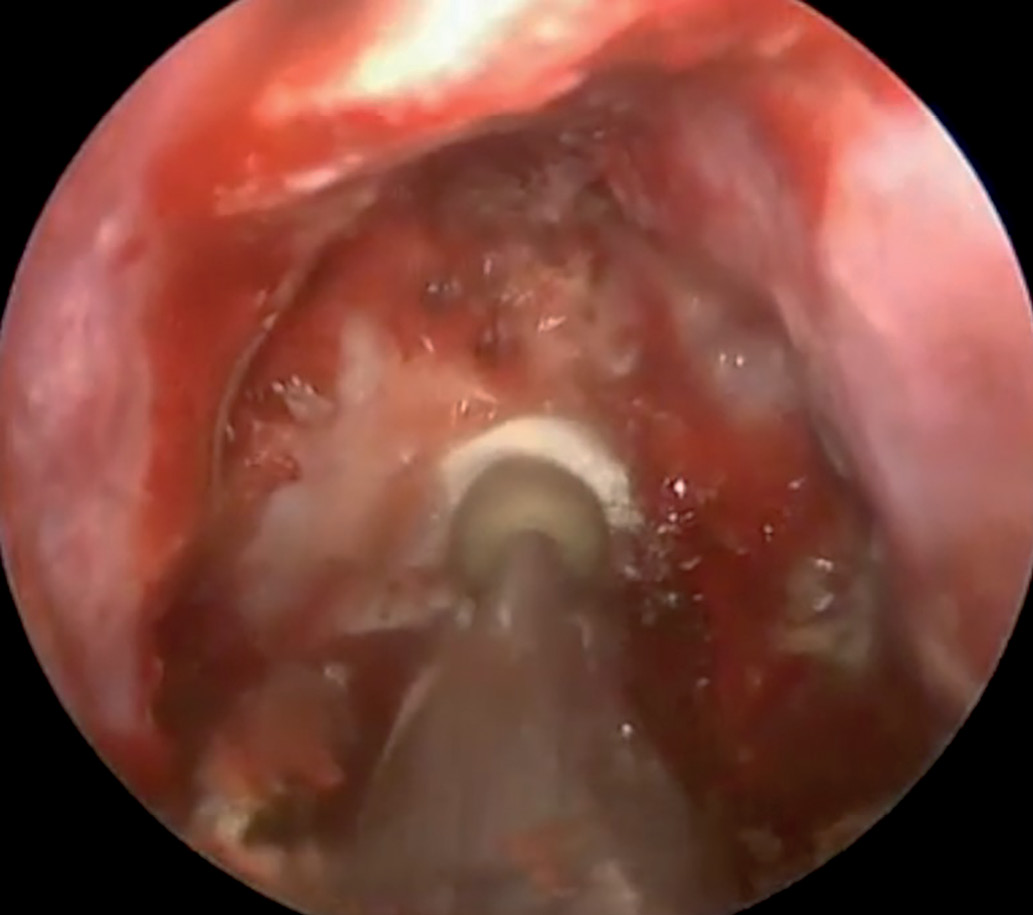

4. Figure 4. The process of removing the tumor from the cavity of the Turkish saddle with the help of an aspirator (T - dura mater, O - tumor, A - aspirator). | |